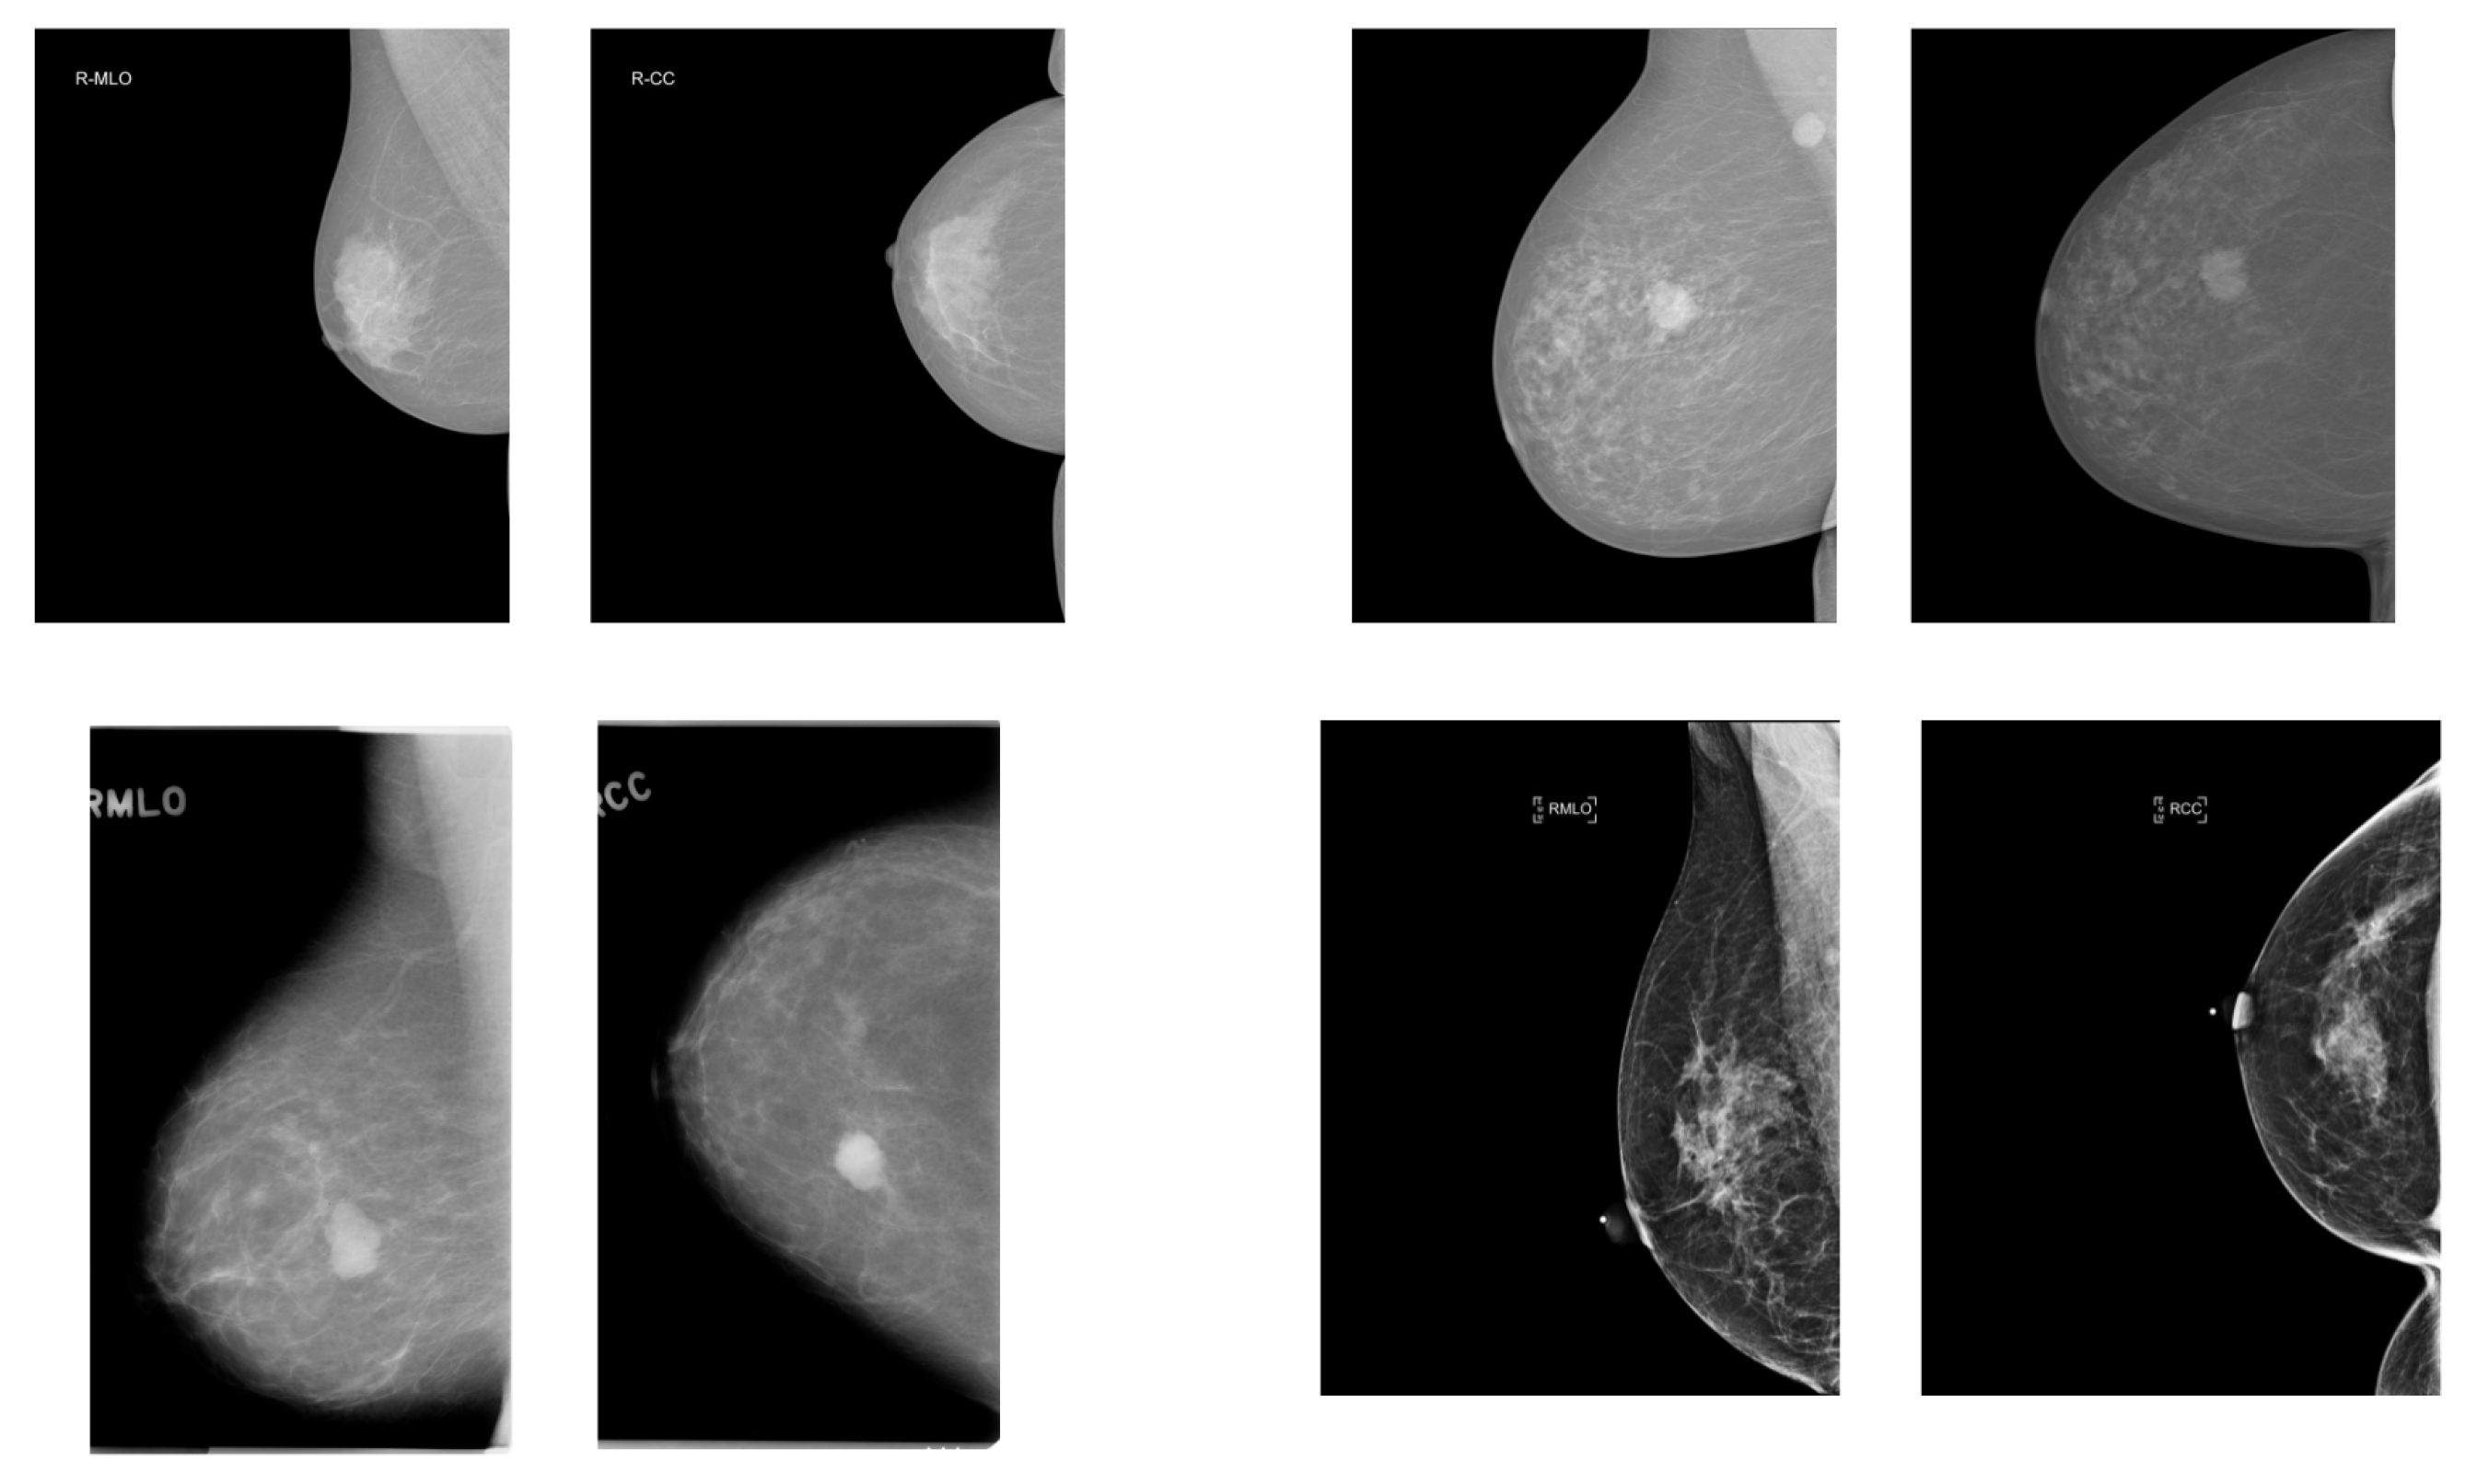

3.1. Datasets

3.2. Preprocessing and Augmentation

3.2.1. CLAHE Algorithm

3.2.2. Cropping Algorithm